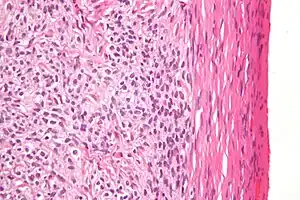

| High magnification micrograph of a thecoma. H&E stain. | |

Low magnification micrograph of a thecoma showing compression of the ovarian cortex (right of image). H&E stain.

Microscopically, the tumour cells have abundant lipid-filled cytoplasm.